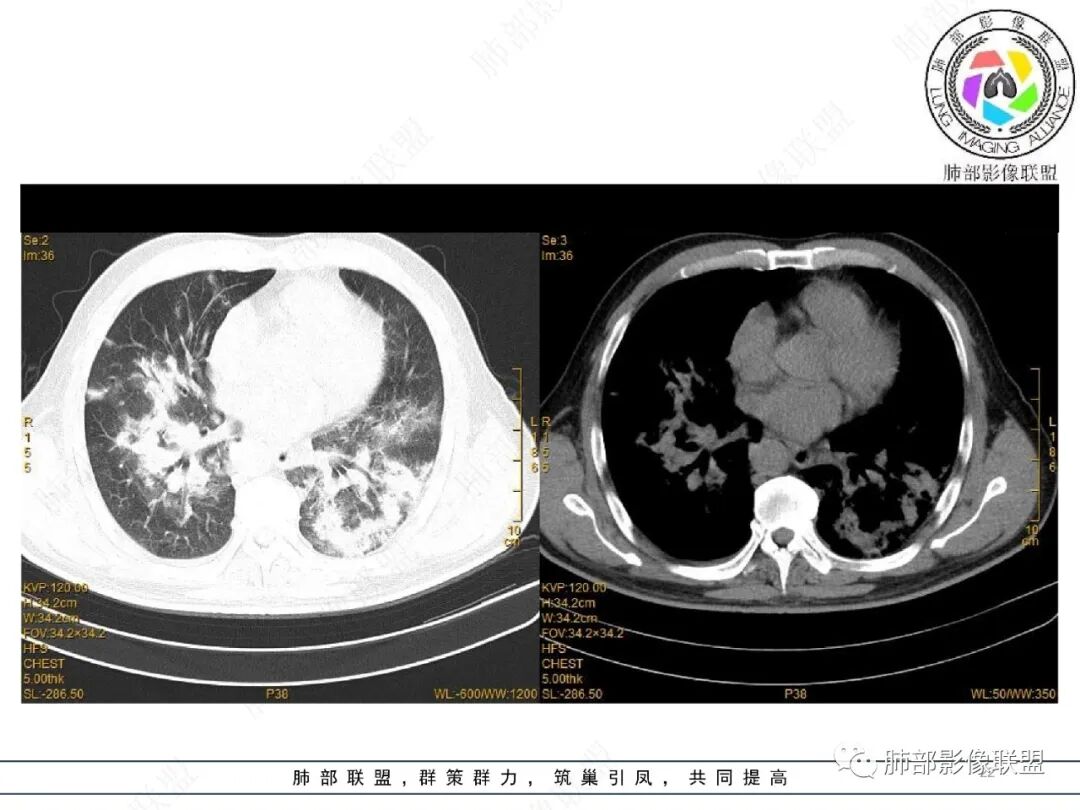

2022.2.17CT显示两肺中内带多发结节影、斑片影、条索影,部分病灶侧向融合与胸膜平行。部分病灶沿着支气管血管束分布、其内支气管稍扩张。部分病灶呈反晕征。大部分病灶边界显示清晰,部分病灶周围可见边界不清的GGO。2022.4.12CT显示两肺中内带多发结节影、条索状、条带状高密度影,边界收缩平直凹陷,大部分病灶沿着支气管血管束分布,亦有位于胸膜下侧向融合与胸膜平行的病灶。总体与第一次CT对比两肺病灶明显吸收。

老年男性,两肺多发病灶,整体呈OP样改变,至于是原发性还是继发性的OP,需要临床鉴别。此病例穿刺结果是隐球菌。该病例CT上缺乏隐球菌典型的“在那遥远的胸膜下,多个蘑菇兄弟,可以侧向融合呈长串状与胸膜平行”影像表现,更多是OP样改变,仅凭临床表现或影像资料诊断隐球菌难度比较大。当然也不除外二元论,导致隐球菌的影像表现被掩盖。